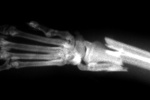

Bonifacy został naprawiony za pomocą drutu chirurgicznego. Podczas

operacji spał |